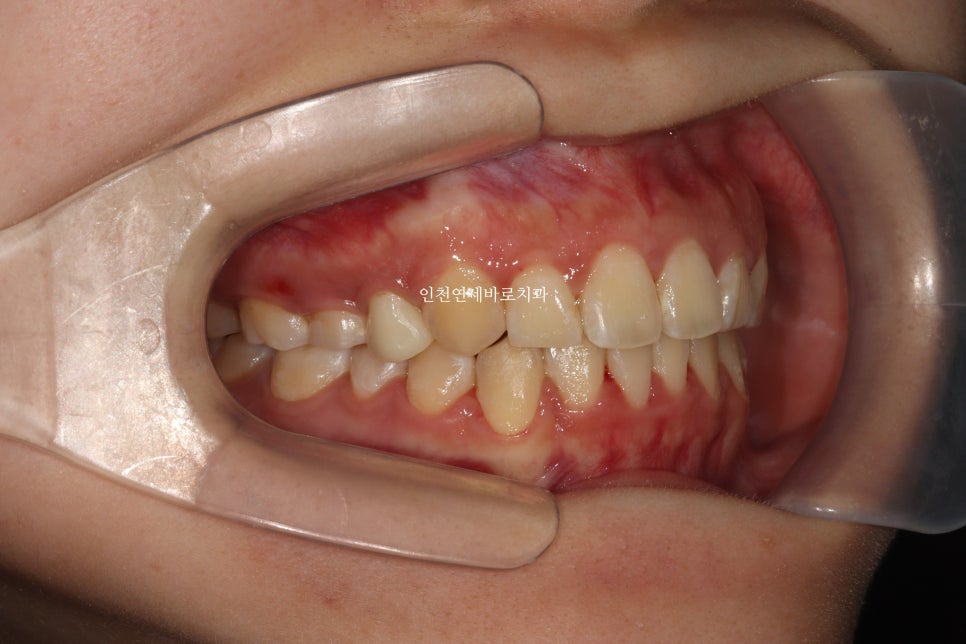

재제작했던 두번째 세트까지 모두 마무리 후

임플란트의 머리, 충치치료했던 치아의 크라운까지 모두 치료를 마무리 한 모습입니다.

재제작 전에 비해 정리된 교합을 확인할 수 있죠?